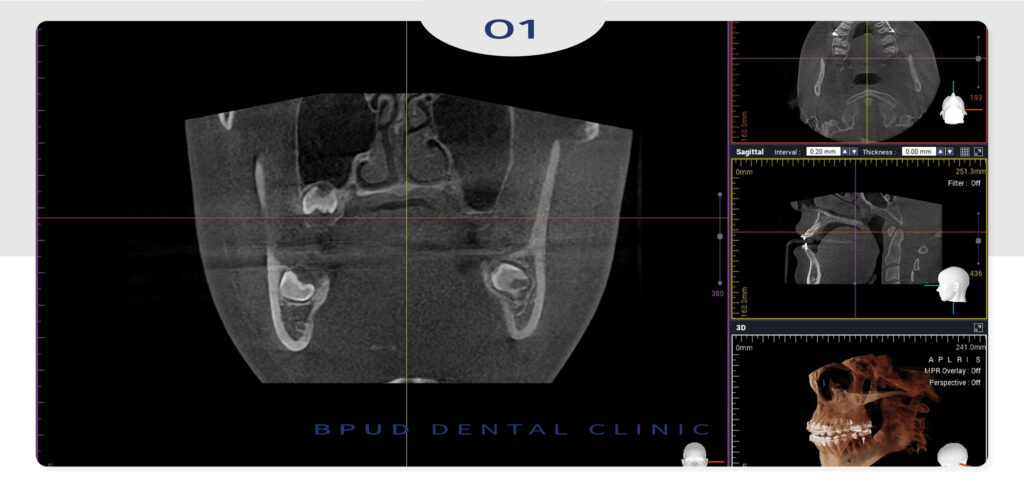

이에 따라 발치 전 정밀한 평가는 필수로

일반적으로는 파노라마 엑스레이로 전체 위치를

확인한 뒤, CT 촬영을 통해 신경과 뿌리,

인접 치아와의 거리를 입체적으로 분석해

위험도를 분류하게 됩니다.

3D CT 촬영을 통해 정밀한 검진 후